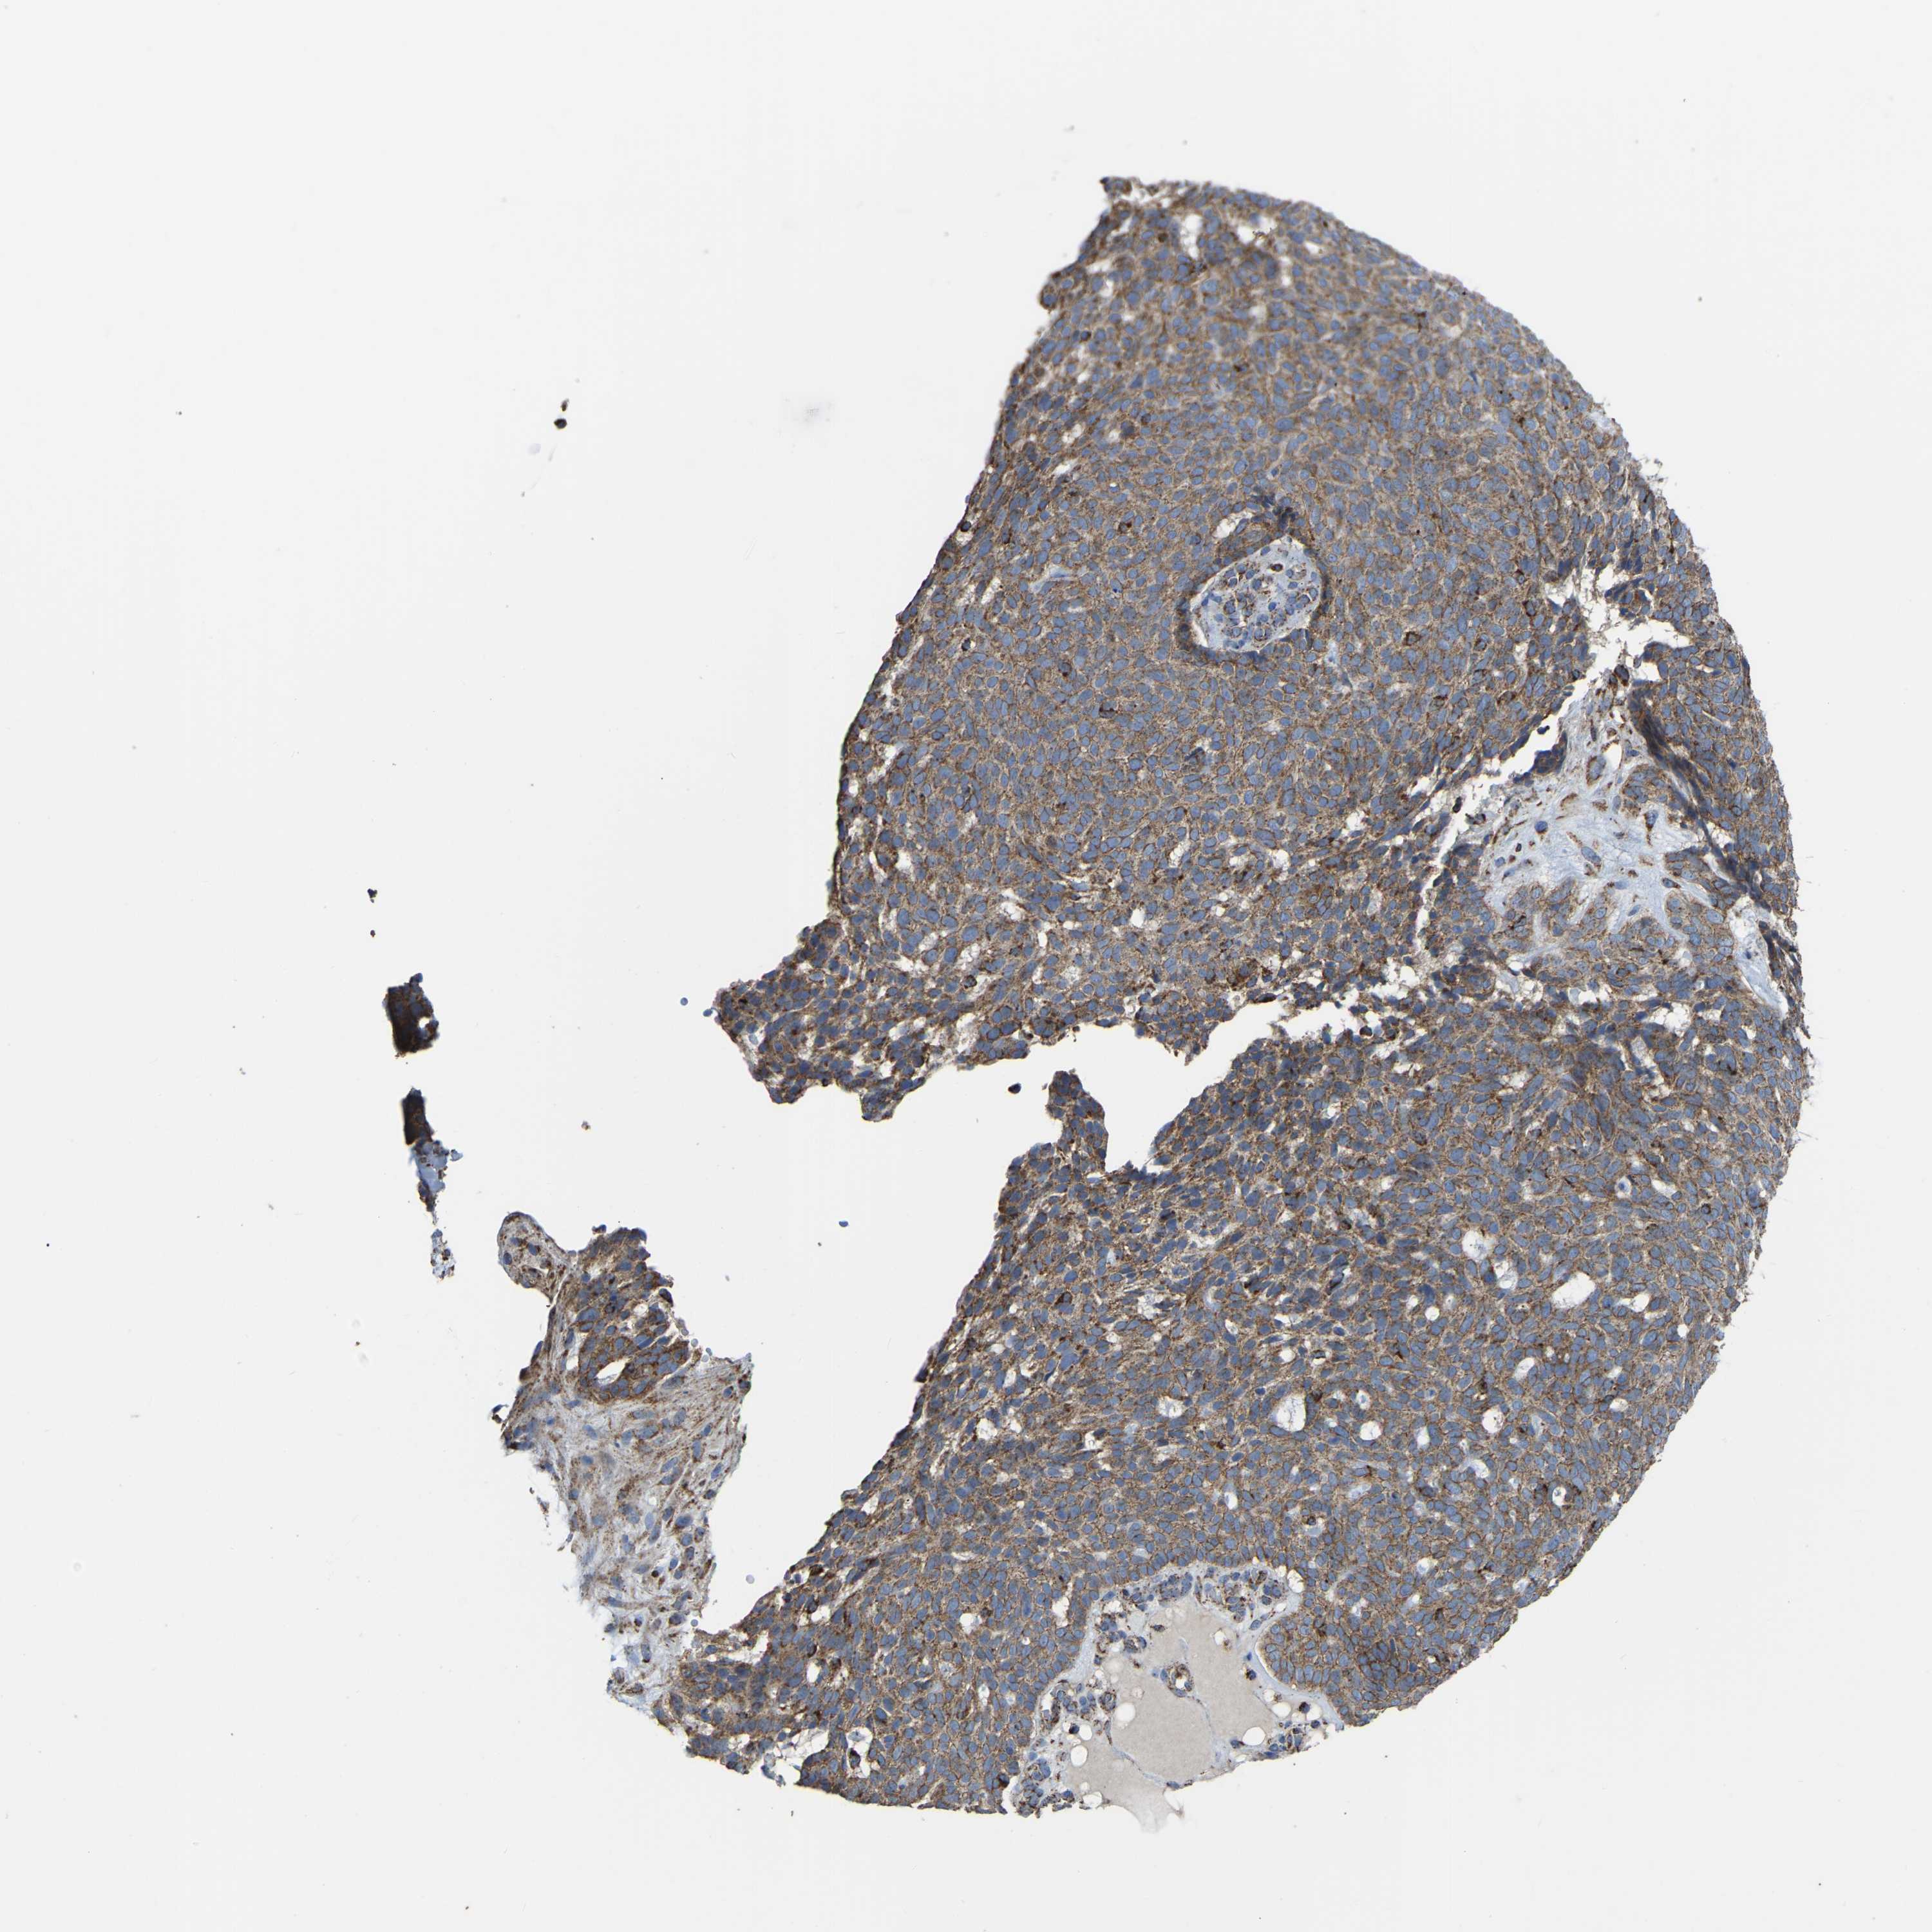

SKIN CANCER - Protein expressioni

A mouse-over function shows sample information and annotation data. Click on an image to view it in a full screen mode. Samples can be filtered based on level of antibody staining by selecting one or several of the following categories: high, medium, low and not detected. The assay and annotation is described here.

Antibody stainingi

Antibody staining in the annotated cell types in the current human tissue is reported as not detected, low, medium, or high, based on conventional immunohistochemistry profiling in selected tissues. This score is based on the combination of the staining intensity and fraction of stained cells.

Each image is clickable and will lead to virtual microscopy that enables deeper exploration of all samples and also displays staining intensity scores, fraction scores and subcellular localization as well as patient and tissue information for each sample.

Antibody HPA018993

Squamous cell carcinoma, NOS